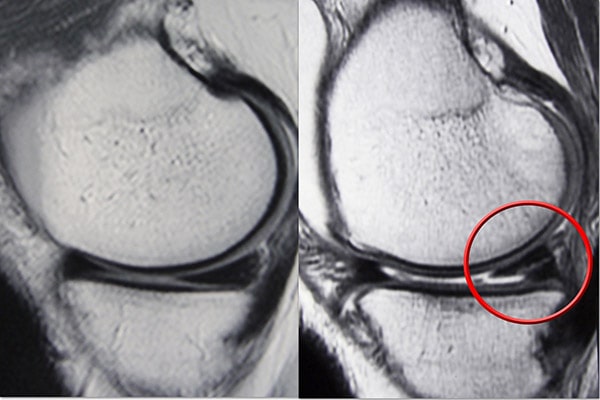

Μαγνητική τομογραφία (MRI). Η μαγνητική τομογραφία αξιολογεί τους μαλακούς ιστούς στην άρθρωση του γόνατος, συμπεριλαμβανομένων των μηνίσκων, του χόνδρου, των τενόντων και των συνδέσμων.

Η μαγνητική τομογραφία είναι η προτιμώμενη μέθοδος διάγνωσης οξείας ρήξης μηνίσκου (ρήξεις που συμβαίνουν λόγω τραυματισμού) λόγω του υψηλού επιπέδου ακρίβειάς της. Εάν η μαγνητική τομογραφία δεν είναι διαθέσιμη ή δεν μπορείτε να κάνετε για άλλο λόγο, ο γιατρός σας μπορεί να παραγγείλει αρθρογράφημα αξονικής τομογραφίας (αξονική τομογραφία όπου εγχέεται χρωστική ουσία) ή υπερηχογράφημα.